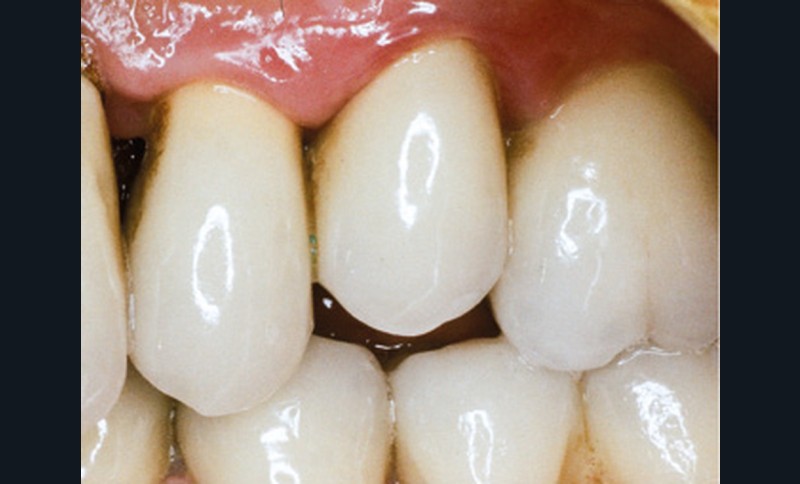

En mars 2016, la patiente se plaint d’une sensibilité sur la 25 et on note cliniquement une inflammation gingivale associée à un décalage apical du rebord marginal et de la ligne muco-gingivale en comparaison de leur situation visualisée au niveau des coiffes supra-implantaires. La couronne clinique est réduite et une infraposition avec une inocclusion d’environ 2 mm par rapport au plan d’occlusion et aux dents antagonistes est également notée (fig. 2 à 4). Un saignement au sondage ainsi qu’une poche de 5 mm en distal sont constatés. Le test de percussion est positif. Les tissus péri-implantaires adjacents ne présentent aucun signe de mucosite.

La radiographie péri-apicale au long cône confirme, sur la 25, un élargissement desmodontal, notamment en distal, des niveaux osseux mésio-distaux réduits par rapport aux clichés de contrôle précédents (les radiographies sont réalisées avec une technique parallèle avec des angulateurs de Rinn non personnalisés), un apex radiculaire normal et des niveaux osseux stables sur les implants adjacents (fig. 5). Le cisaillement systématique du fil dentaire lors de son passage confirme des points de contact très étroits entre 24, 25 et 26.